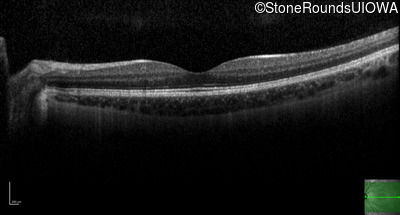

Optical Coherence Tomography - Right - 20/16 -1

Exemplar / OCT Stack

OCT Stack